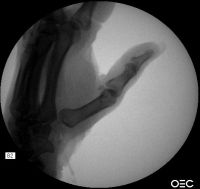

| 8 months postop. The

trapeziectomy defect height is still maintained. |